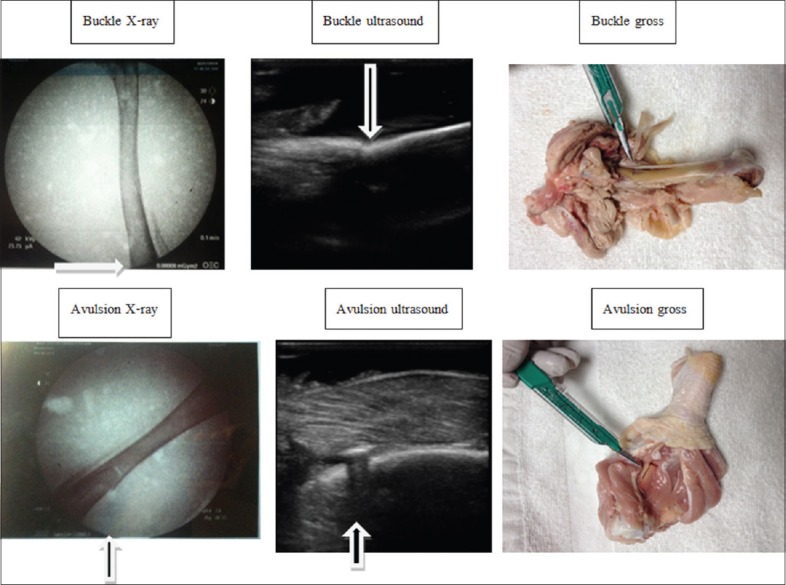

This was an IRB-approved, randomized prospective study. Study participants included 40 EM residents at a single site. Fractures were mechanically induced in five chicken legs, and five legs were left unfractured. Chicken legs were imaged by both modalities. Participants were given 2 min to view each of the images. Participants were randomized to either US or X-ray interpretation first and randomized to viewing order within each arm.

EM residents were better able to identify fractures using US compared to X-ray, especially as level of US and ED experience increased. These results encourage the use of US for the assessment of isolated extremity injury, particularly when the injury is diaphyseal.